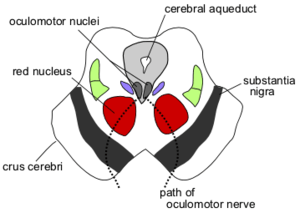

Section through superior colliculus showing path of oculomotor nerve. Periaqueductal grey is the grey area just peripheral to the cerebral aqueduct. | |